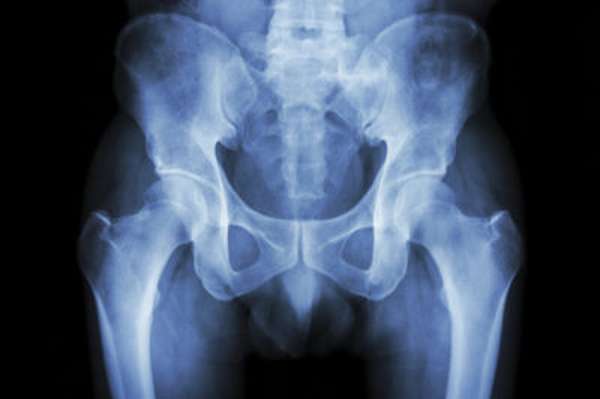

Рентгенологическое исследование прямой кишки (ирригоскопия) позволяет обнаружить опухоли, сужение просвета толстого кишечника. Рентгенография также применяется для визуализации состояния копчика и крестца, костей таза, тазобедренных суставов. На рентгенограмме можно обнаружить следы перелома копчика, вывихов (подвывихов), участки остеопороза и другие патологии костной ткани.